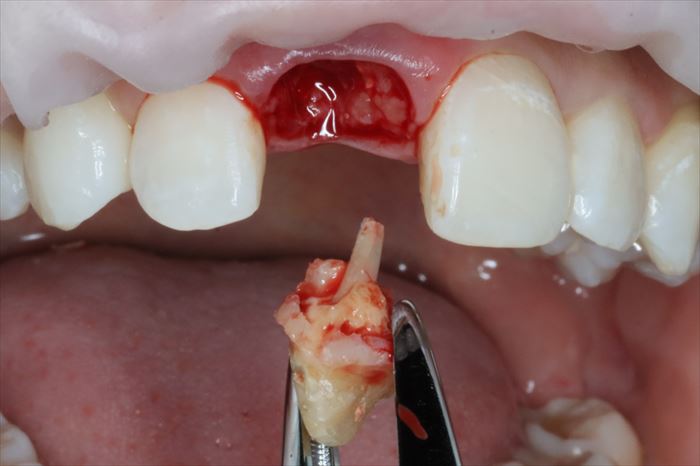

残っていた歯根を抜歯し、顕微鏡下で抜歯窩内部の掻爬を終えました。

心配していた唇側の骨は無事に保存できました。

このように満身創痍な状態で今日までよく頑張ってくれました。